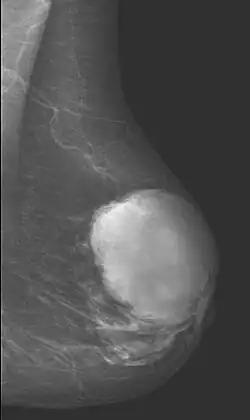

Cystosarcoma phylloides

Das Cystosarcoma phylloides (synonym Phylloidtumor), auch Zystosarkom (der Brust) genannt, ist ein seltener Tumor an der Brust (Mamma) der erwachsenen Frau. Er hat Anteil von ca. 1 % an allen Brustdrüsentumoren.

Der Tumor zeigt sich als finger- oder keulenartige Wucherung des Bindegewebes und der Brustdrüse. Er wird als Sonderform des Fibroadenoms (gutartige Geschwülste der weiblichen Brust) angesehen. Phylloidtumore sind aber oft größer als diese und wachsen mit fingerartigen Ausläufern in das umgebende Brustgewebe. Der Tumor wächst (meist schnell) in Schüben und kann zu erheblicher Brustdeformation führen und auch die ganze Brust befallen.

Die Knoten des Tumors sind meist gut zu ertasten. Die Oberfläche ist sehr unregelmäßig. Der Tumor kann durch die Haut „blumenkohlartig“ nach außen gelangen. Da der Tumor sehr schnell wächst, kann er zu einer erheblichen Brustvergrößerung führen.

Zur Abgrenzung zum Fibroadenom reichen Mammographie und Sonographie nicht aus. Erst andere bildgebende Verfahren wie MRT und eine Gewebeprobe (Biopsie) ermöglichen die sichere Diagnose. Die Klassifikation der Bösartigkeit basiert auf dem Anteil der entarteten Zellen.